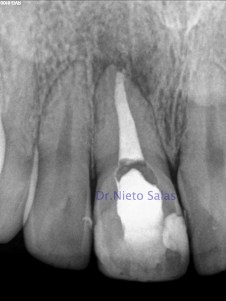

Nos llega a la consulta un caso de un 1.1 con fístula vestibular. Hablamos con el paciente y nos refiere en la historia del diente un traumatismo hace muchos años. Hacemos las pruebas de rutina para evaluar el caso.

Vemos una fractura en el tercio apical con una periodontitis apical crónica y el sondaje es negativo.

Se le plantea la siguiente posibilidad al paciente, tratamiento solo del tercio coronal y no tocar el tercio apical, pero si diese problemas el fragmento apical deberíamos hacer una resección del mismo con cirugía, aprovechando a evaluar el sellado del fragmento coronal y si fuese necesario mejorarlo vía apical, que hay mayor control.

De esta manera, el material de elección vuelve a ser el M.T.A., nos va a aportar las mismas propiedades que en el caso anterior.

Volvemos a usar un medicamento intraconducto para crear mejores condiciones extra radicular y lo citamos a los 15-20 días.

El trayecto fístuloso ha desaparecido, y sellamos el conducto con M.T.A. colocandolo con ayuda de la magnificación. En este caso solo obturaremos con un solo material.

(orto) (disto)

Nos aseguramos del sellado.

En la revisión a los 10 meses, podemos observar la regeneración ósea de los tejidos periapicales. Las imágenes radiopacas, es muy probable que se trate de la superposición del corte de la raíz (he señalado con un circulo rojo) aunque podría ser cuestionado, saldríamos de dudas con un CBCT.

Si lo comparamos con a inicial: